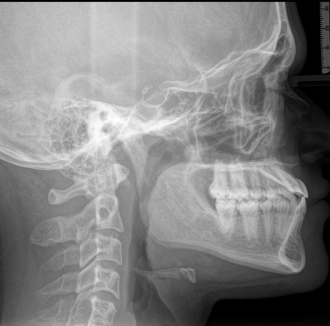

Advancement of both jaws ( dont exactly now how much)

Maxillary downgraft ( short face syndrome ) CW rotation (dk exactly this concept)

Advancement of both jaws ( dont exactly now how much)

Maxillary downgraft ( short face syndrome ) CW rotation (dk exactly this concept)